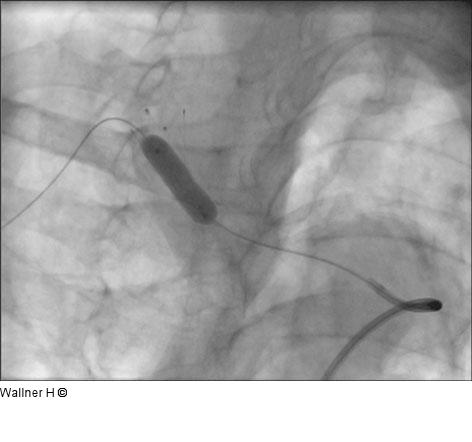

Abbildung 5: Postdilatation Postdilatation (Pheron™, Biotronik, 8x20 mm/135 cm) |

Postdilatation (Pheron™, Biotronik, 8x20 mm/135 cm) |